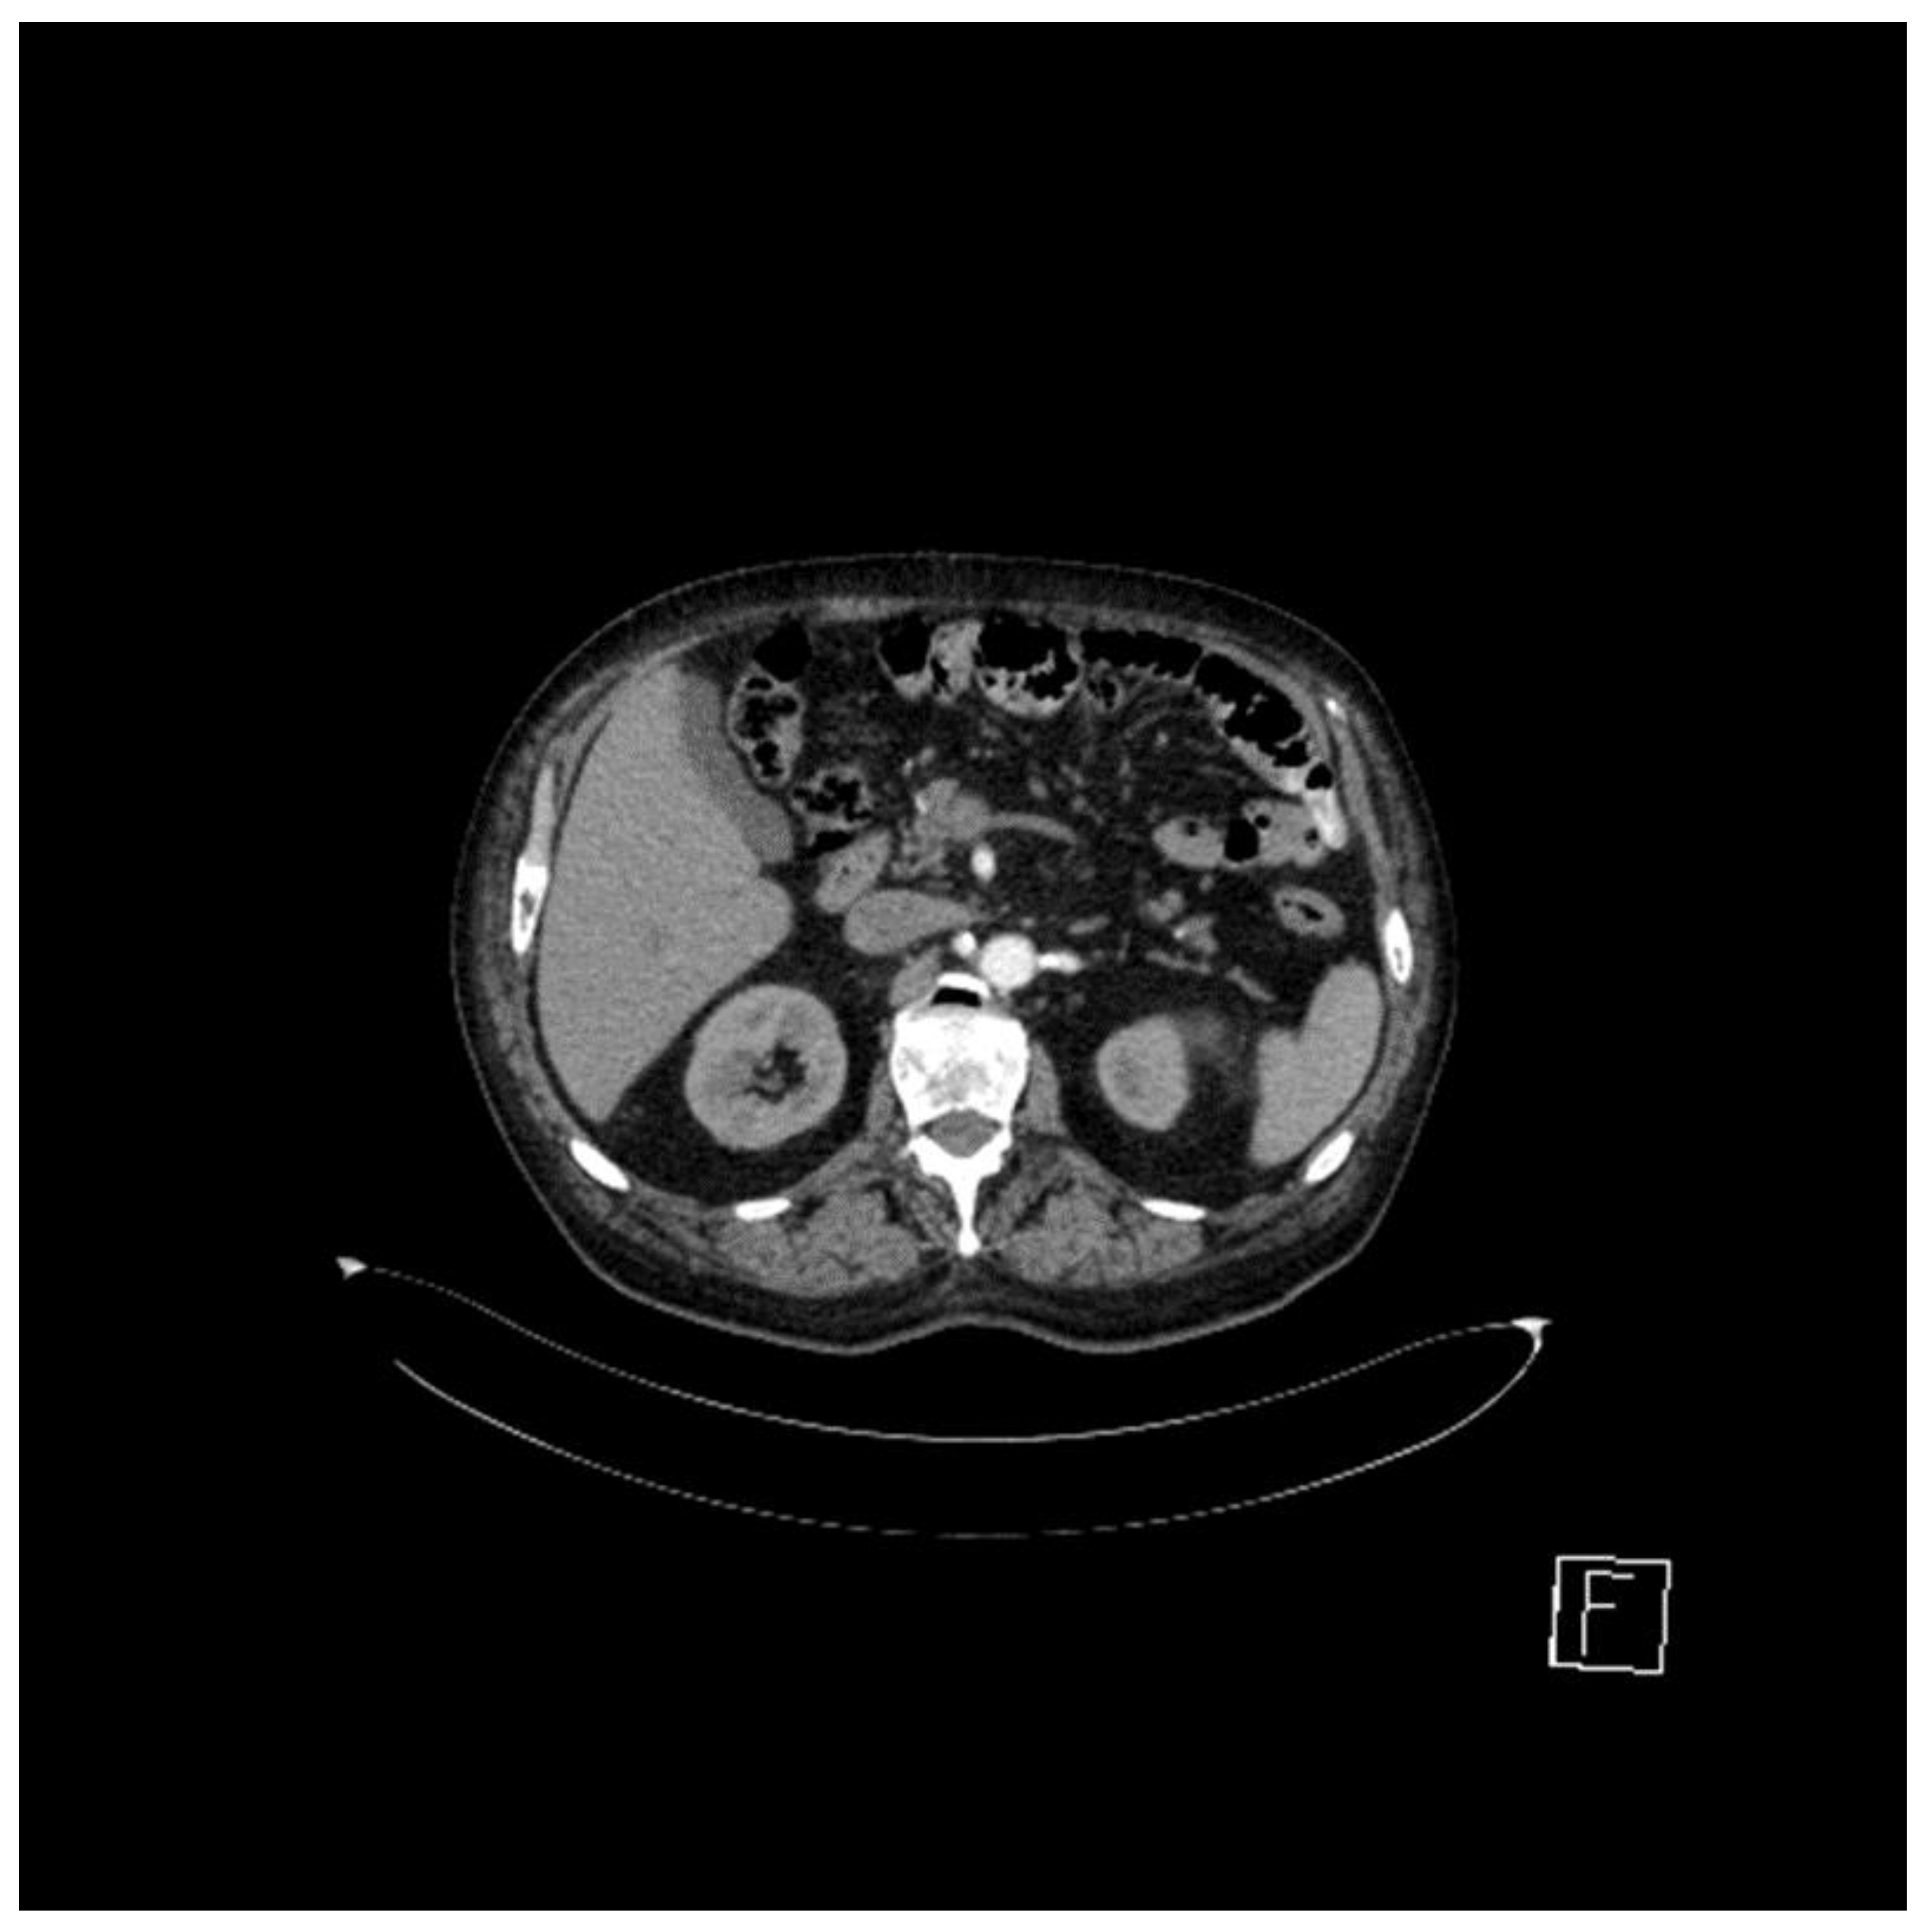

However, in September 2019, the follow-up computed tomography indicated the need to perform bone scans for newly appearing suspicious lesions at the costal level, which revealed left costal osteogenic reactions that had recently appeared (Figure 1).

Small hypercapture foci located at the level of the left antero-lateral costal rib cage CVI, chondro-costal CVII, and posterior left CVII, CVII, and CIX—the changes had various intensities and dimensions—represented the metabolically active aspect.

Figure 1. Bone scan (September 2019).